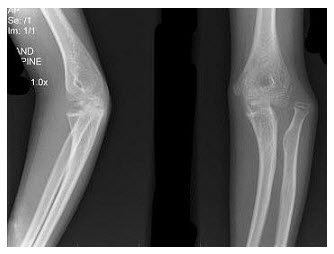

139、单项选择题

男,11岁,左肘外伤,根据所示图像,最可能的诊断是()

A.左肱骨内上髁骨骺Ⅰ度分离

B.左肱骨内上髁骨骺Ⅱ度分离

C.左肱骨内上髁骨骺Ⅲ度分离

D.左肱骨内上髁骨骺Ⅳ度分离

E.左肱骨内上髁骨骺Ⅴ度分离

140、单项选择题